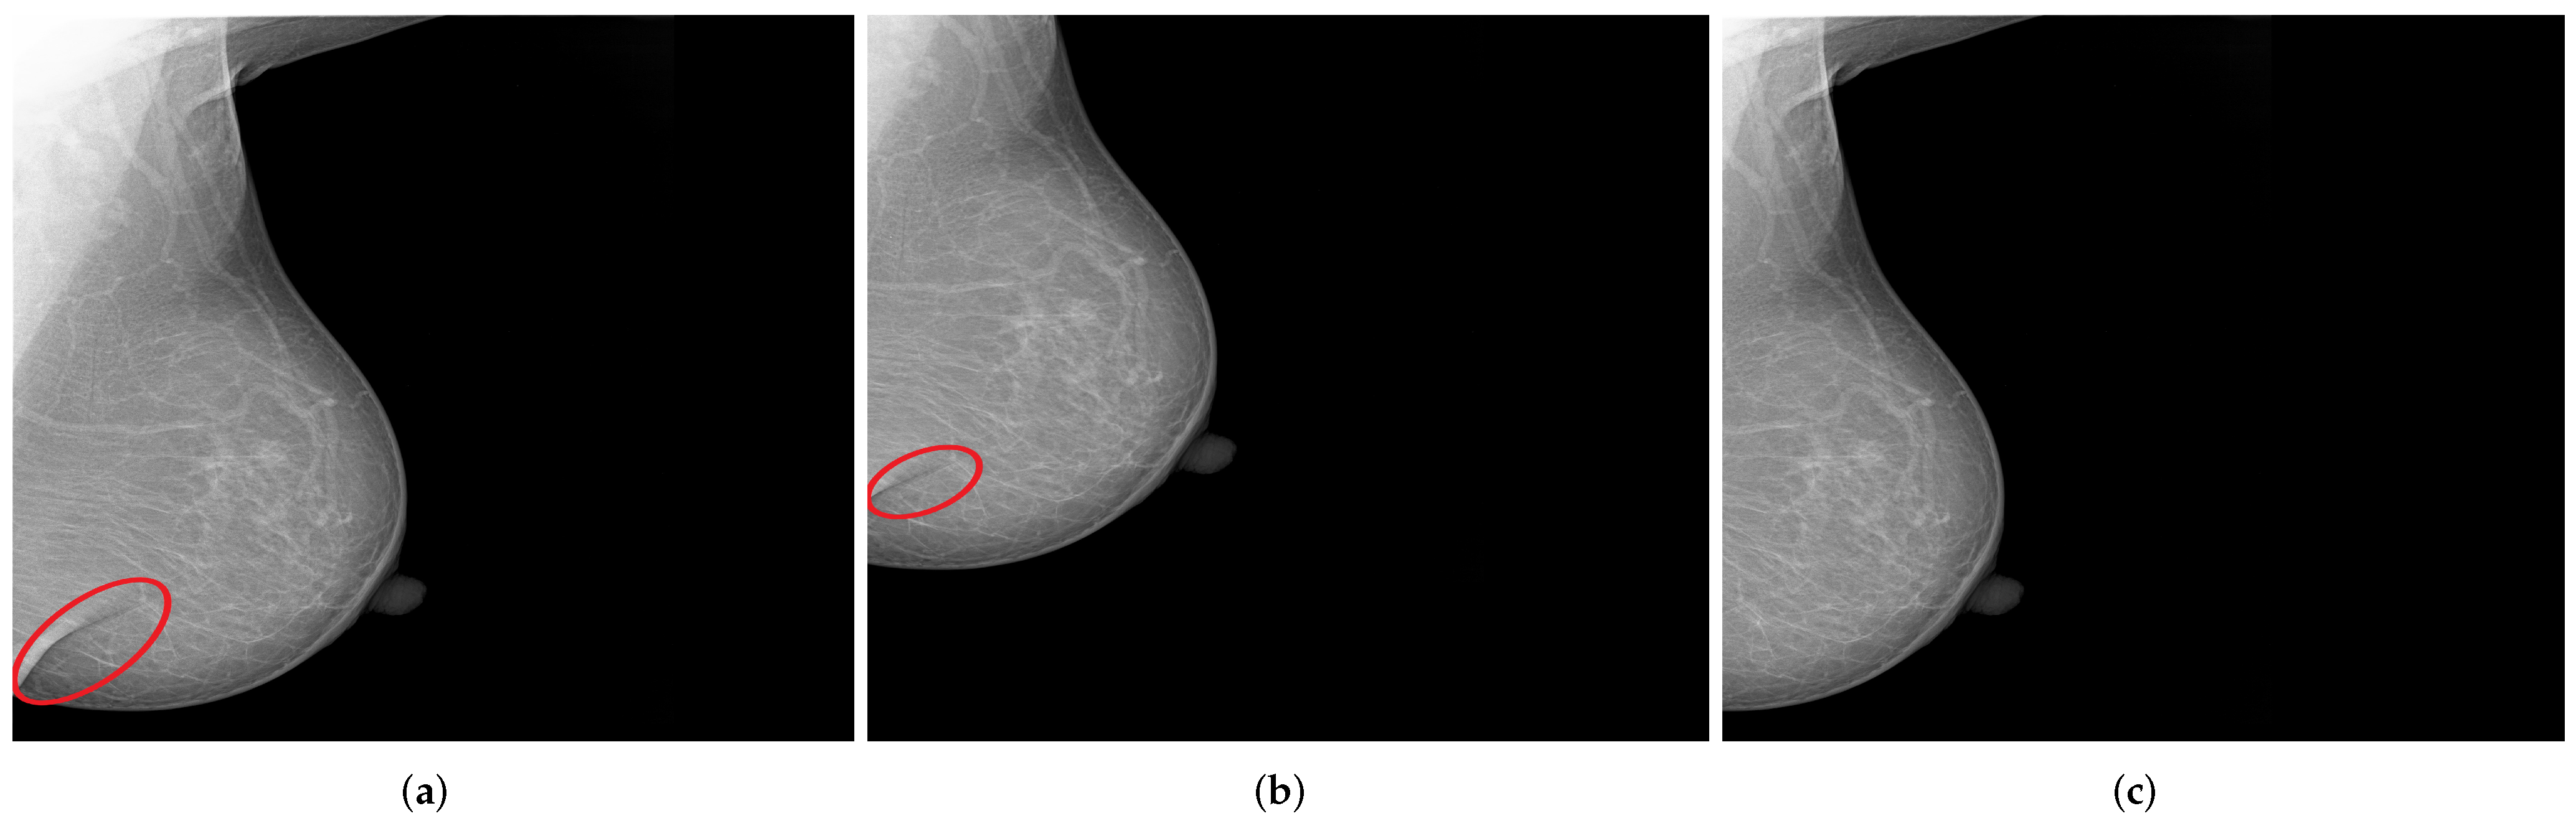

3.4. MLO: Coverage of All Relevant Breast Tissue

3.6. CC: Coverage of All Relevant Breast Tissue